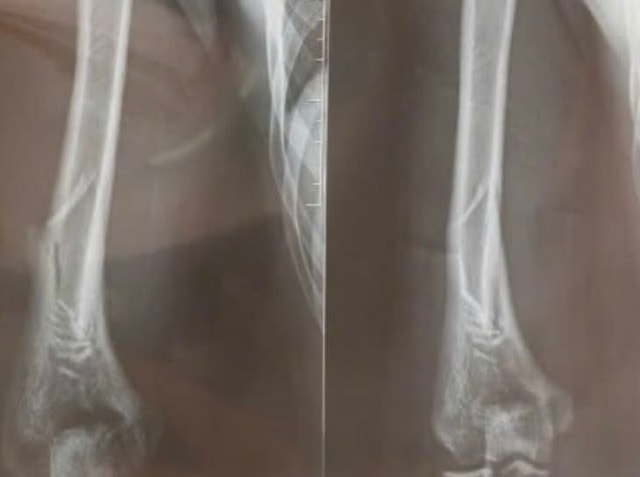

Nam thanh niên 18 tuổi nhập viện trong tình trạng đau vùng cánh tay phải sau khi chơi vật tay với bạn.

Theo TS.BS Nguyễn Trọng Nghĩa, Khoa Chấn thương chỉnh hình, Bệnh viện Đa khoa Hà Đông, trò chơi vật tay tiềm ẩn nhiều nguy cơ chấn thương. Khi vật tay, lực xoắn mạnh tập trung vào phần giữa xương cánh tay, đặc biệt là vị trí có rãnh xoắn. Điều này dễ dẫn đến gãy xương kiểu xoắn. Thần kinh quay chạy qua khu vực này, nên nếu bị tổn thương, có thể gây yếu hoặc liệt các cơ duỗi ở cổ tay và ngón tay.

Khi chơi vật tay, lực lớn dồn vào cánh tay khi khuỷu tay cố định, gây áp lực mạnh lên phần 1/3 dưới xương cánh tay, nơi dễ bị gãy nhất. Nhiều người cố dùng mẹo thay đổi hướng xoắn hoặc tăng, giảm lực đột ngột để thắng đối phương. Điều này làm tăng nguy cơ gãy xương.